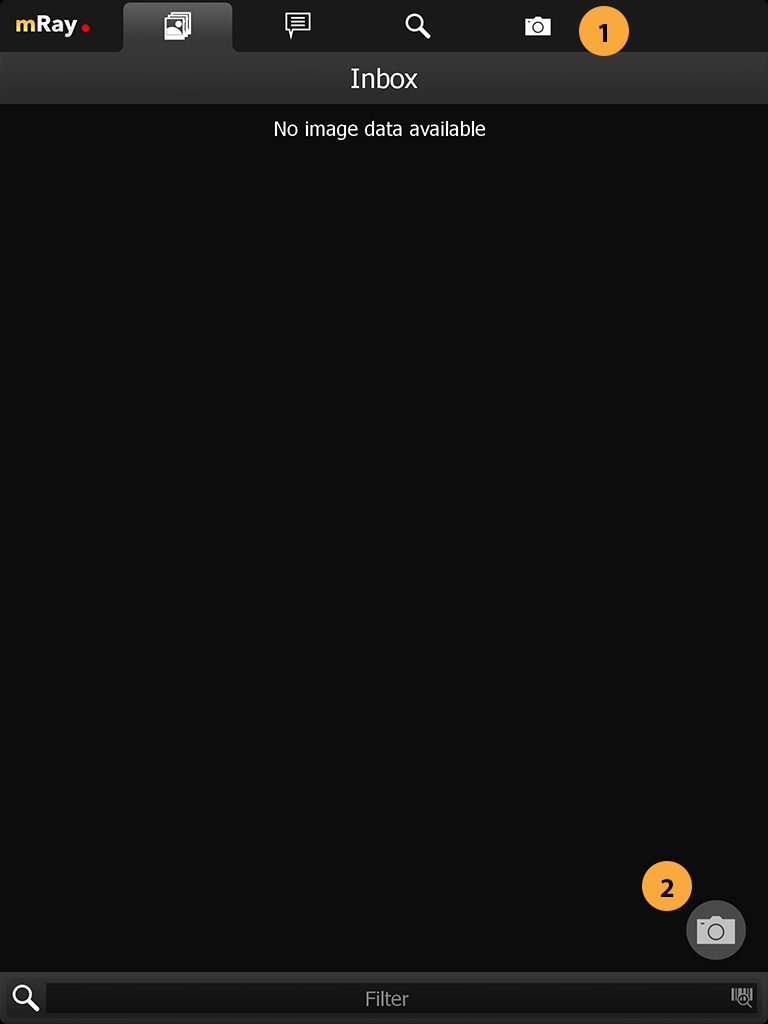

9.1. Inbox

Nach dem Einloggen öffnet sich die „Inbox“ (Inbox). Über diese können Sie den gewünschten DICOM Datensatz selektieren, der Ihnen über den eingestellten Server zur Verfügung gestellt wurde. Sie sehen hier also alle am mRay-Server vorliegenden Daten, auf die Sie Zugriffsrechte haben.

-

Wechseln zur Fotodokumentation

Fotofunktion aufrufen: Siehe Abschnitt Fotodokumentation zur näheren Erläuterung.

-